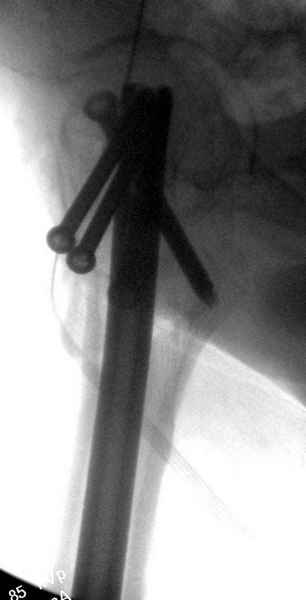

На второй день после выписки упал дома. Снимки приложены. Коллеги рекомендуют удаление шурупа и вытяжение. Что делать?

Привет из солнечного Будапешта с Eurotrauma-2008. Да, замечательный пример. Получается, профилактику расхождения отломков шейки надо было проводить каким-то реконструкционным или проксимальным гвоздем, причем сразу длинной версией. Сейчас, наверно, так и надо бы сделать.

Убрать винты, каким-то джойстиком в вертельной области сделать репозицию шейки, фиксировать ее спицами, а дальше вправлять и фиксировать как вертельный перелом.

Решайте проблемы по мере поступления. На первом этапе решение одно, и на мой взгляд верное. Ситуация изменилась кардинально - другое решение. Я бы избрал ресинтез, убрав винты заменил на Гамму. Что с ним будет послезавтра? - Будем решать послезавтра. Такая наша доля.

Правильно, ситуация изменилась, как говорят у нас теперь "different animal", надо решать проблему подвертельного перелома. При наличии различных вариантов фиксаторов, включая Страйкер Гамма 3, мы выбрали DePuy Antegrade Trachanteric Nail из-за многовариантности проксимальной фиксации и двойного изгиба. Вводится через вертел под 8 градусным углом, и есть достаточный передний диафизарный изгиб, предупреждающий пенетрацию дистального переднего кортекса.